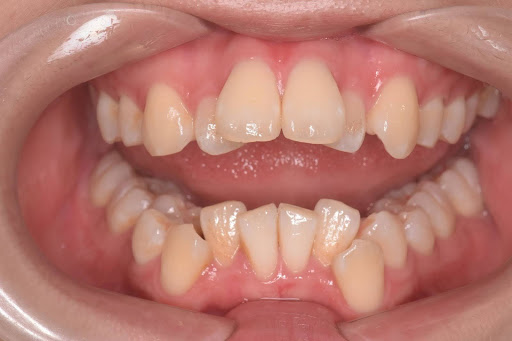

こちらはインビザラインフルプランの術前の写真です。